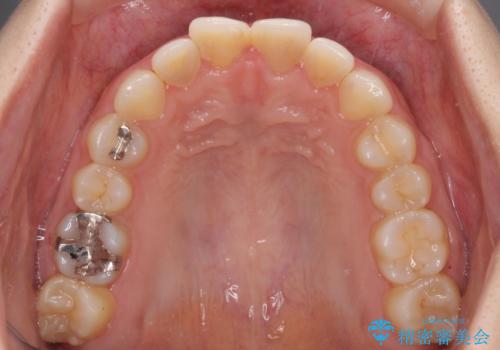

もう少しデコボコを改善したかったのですが、ご本人の希望もあり、装置を除去しました。

後戻りを防止するため、舌側を細いワイヤーによる保定を行いました。